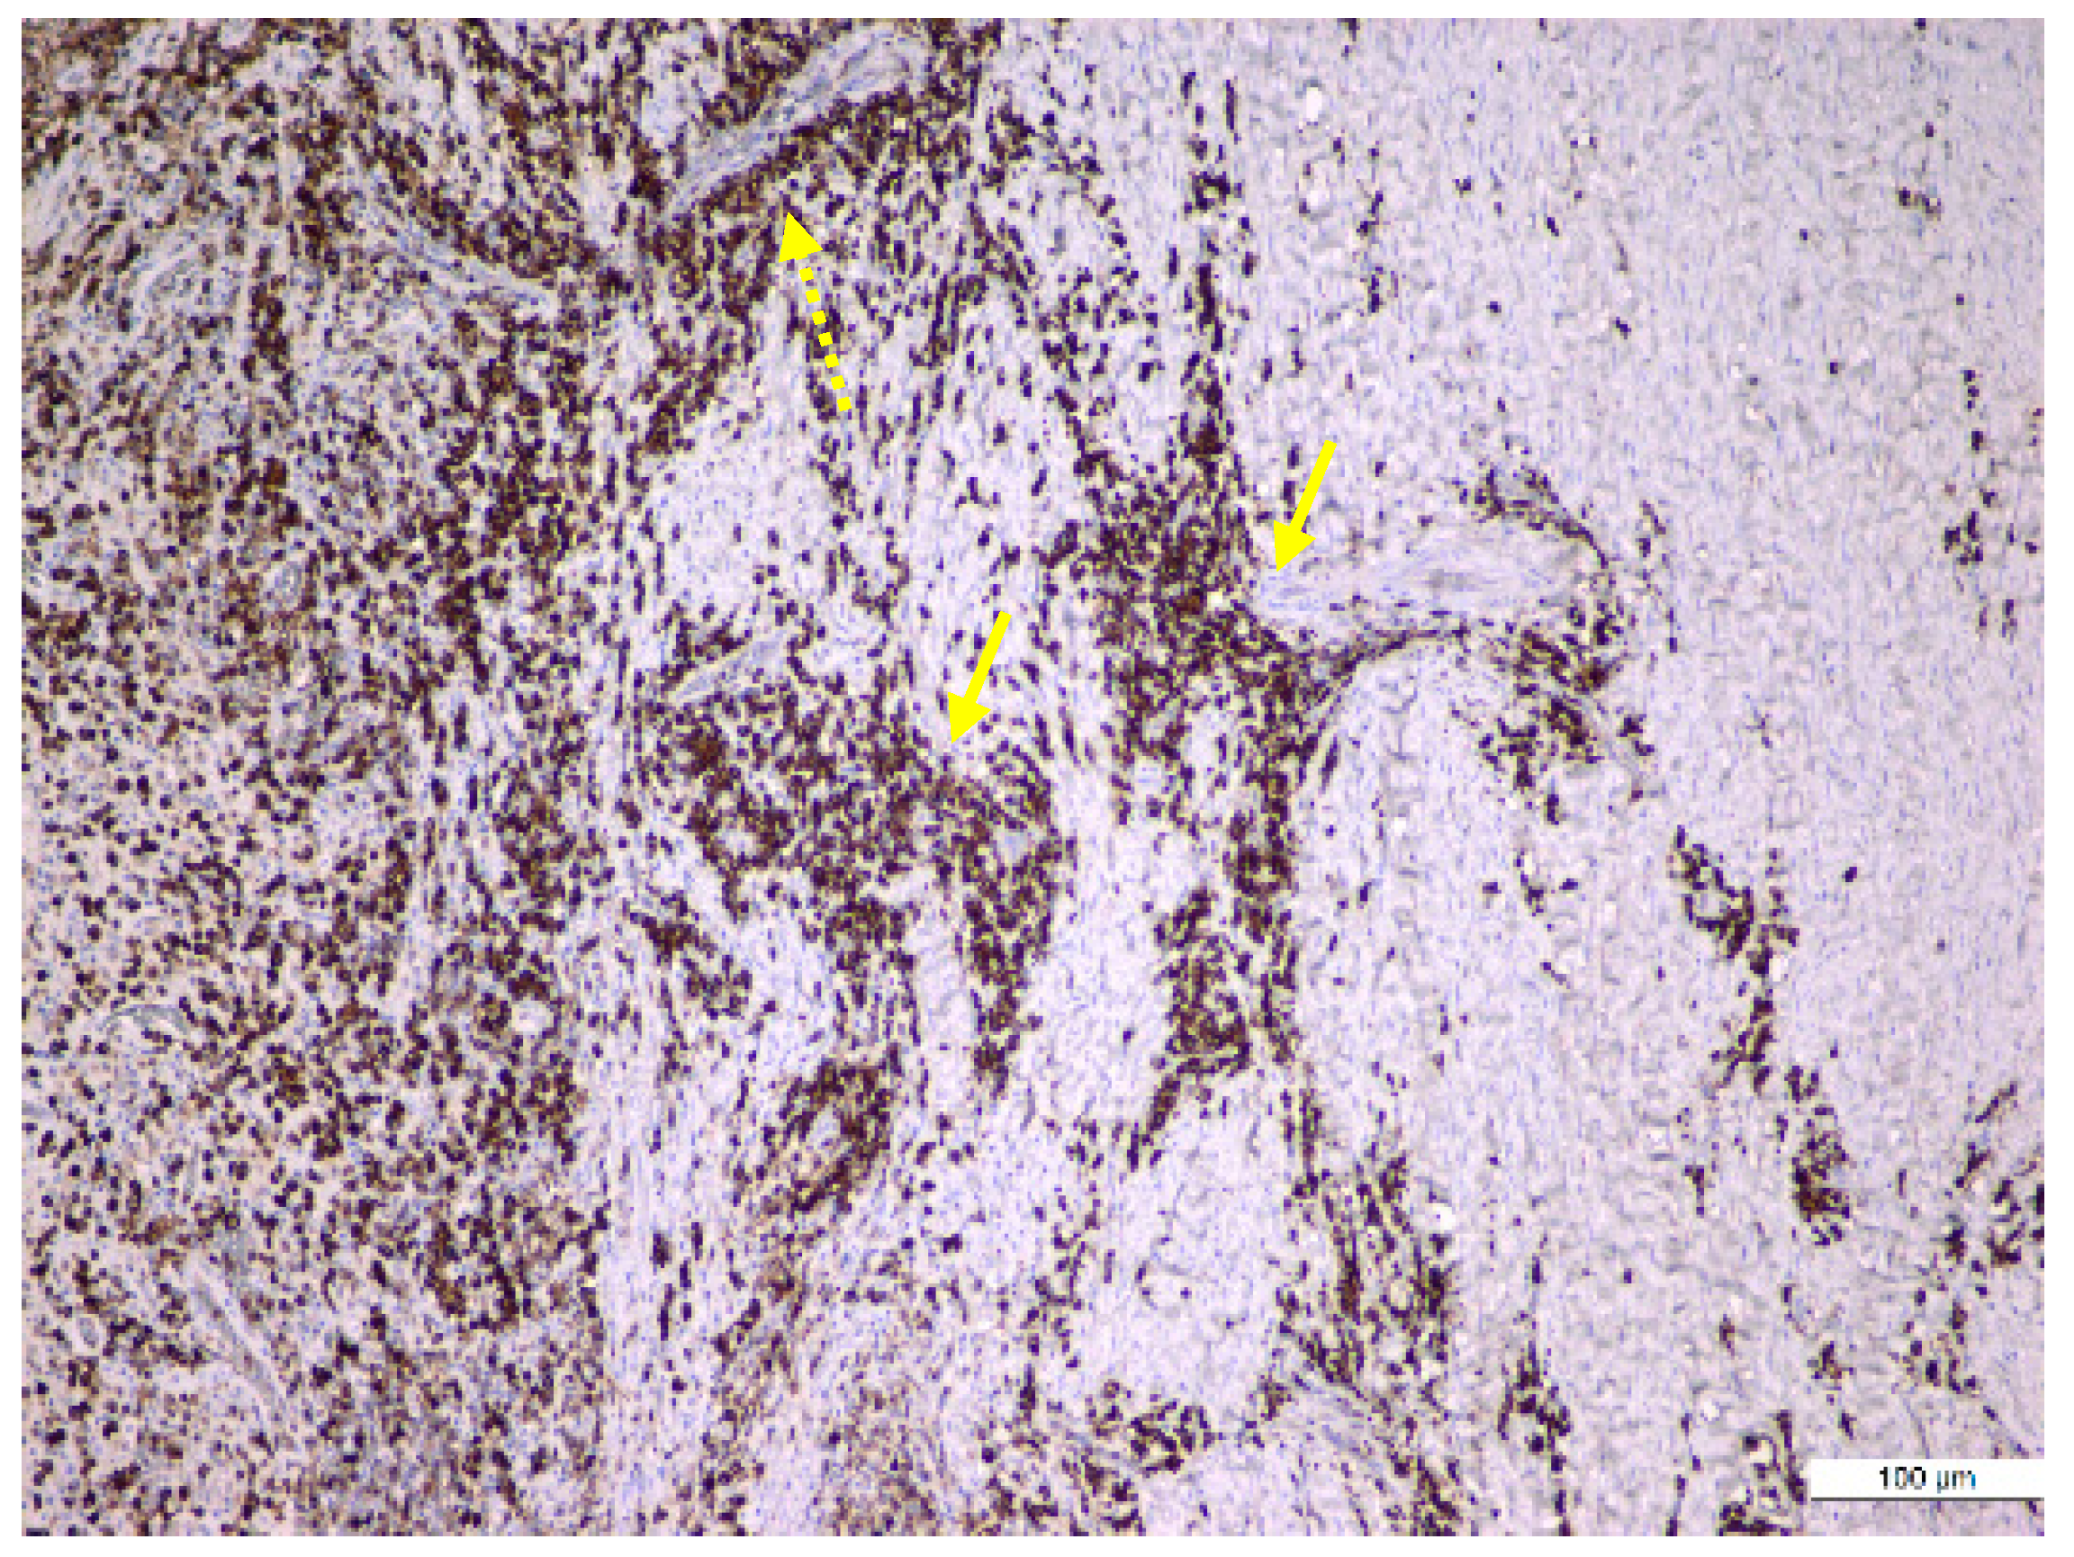

The results regarding the immunopositivity for CD4, CD8, CD20, CD68, and CD79α antibodies showed the following features: CD4+ helper T lymphocytes were distributed in all periapical cysts; CD8+ cytotoxic T lymphocytes were distributed in all periapical granulomas and cysts but were more numerous in the outer wall of the periapical cysts; CD20+ B lymphocytes were present in almost all periapical granulomas but also in the periapical cyst walls; CD68+ macrophages were present in all periapical cysts, mainly in the inner portion (subepithelial zone) of the outer fibrous wall; and in almost all periapical granulomas, CD79α+ B lymphocytes/plasma cells were present in an important number in the periapical granulomas (Figure 6, Figure 7 and Figure 8).

CD68+ macrophages were identified in the entire thickness of the wall but also in the content of the lumen (Figure 6). The distribution of the lymphocytic infiltrate in the lesions was usually diffuse for both types of lymphocytes, but CD4+ helper T lymphocytes showed a follicular pattern in some areas (Figure 7b).

Figure 8. Immunohistochemical identification of the plasma cells in an old periapical granuloma: large sheets of plasma cells infiltrating the mature granulation tissue (yellow arrow), especially around the blood vessels (interrupted yellow arrow) (anti-CD79α antibody, ×100).